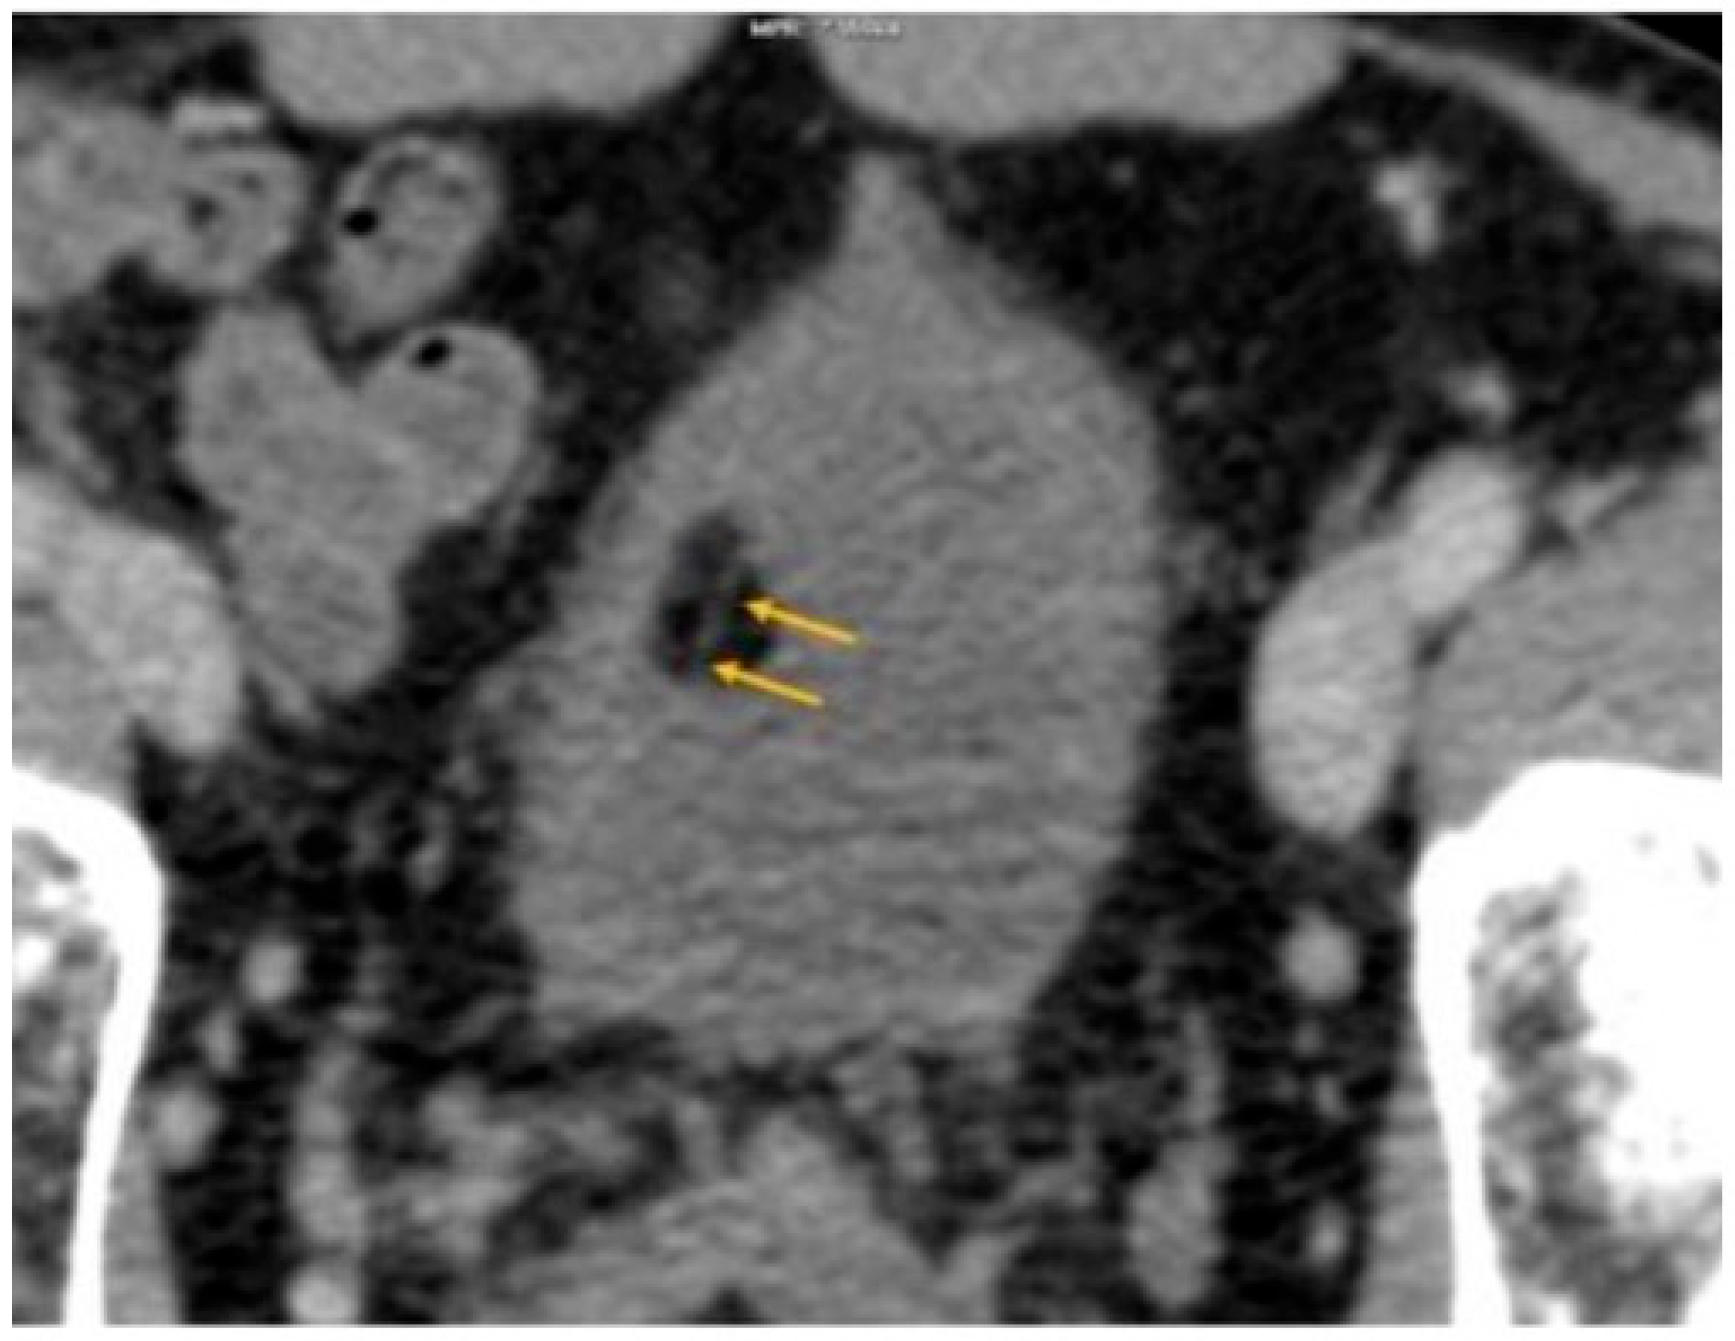

| CT | Homogenous, endophytic, hypodense lesion with smooth margins as viewed in the non-enhanced, venous, or excretory phase (Figure 2). Fat attenuation of the lesion ≤ −20 HU, which is diagnostic of lipoma (usually −50 to −150 HU). | -Erich K. Lang et al. reported that in an excretory phase CT generating 5 mm thick slices demonstrated 7 to 9 mm grape-like lesions, with attenuation coefficient ranging from −60 to –160 HU found in the trigone region [14]. -The presence of septations as reported by Paniagua et al. (Figure 5) raised suspicion of malignant liposarcoma, which would require surgical intervention [22]. |